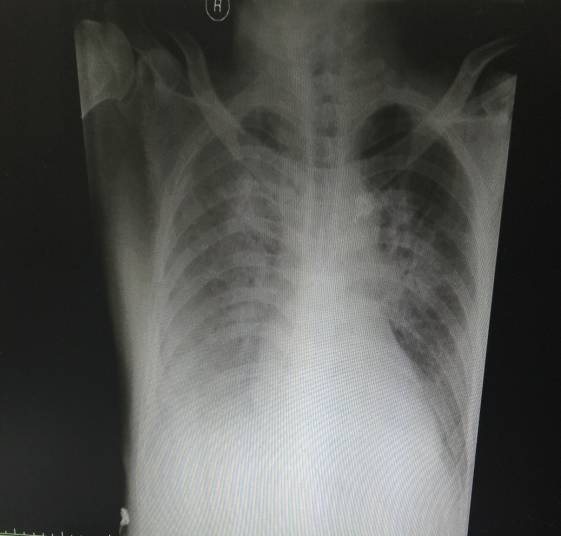

胸片(术前1月):